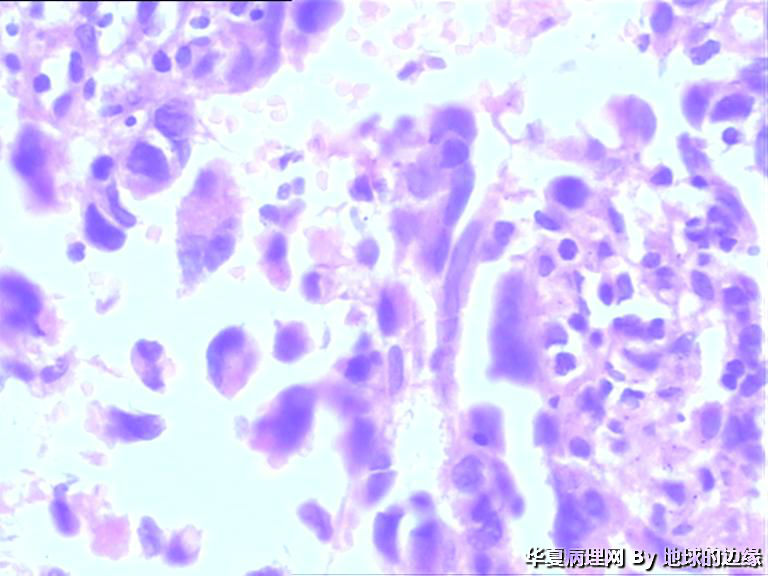

病人女性,48岁

MRI示:右肱骨肿瘤待排,包块大小为10x8cm,活动度差,边界欠清,鱼肉组织(白色),肿块侵犯至骨外    组  织。

恶性。是转移还是原发,是骨肉瘤还是浆母?需要进一步资料并标记。

考虑肉瘤,转移癌也排除一下吧

目前Vimentin阳性,P53阳性,AFP,EMA,CK7,CK20,E-ca,CR,PLAP,CD99,ER,PR,CEA,均阴性,只是没做淋巴瘤这一套了